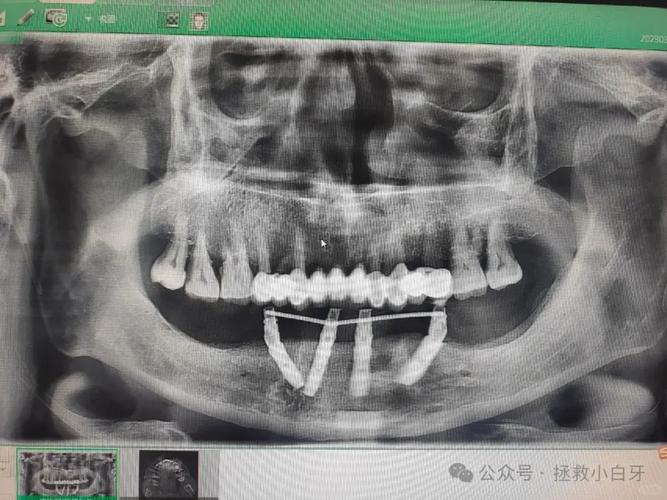

- 影像学检查:CBCT(锥形束CT)是核心检查,可三维重建颌骨结构,精确测量骨高度、宽度、密度,以及神经管、上颌窦等重要解剖结构的位置,指导种植体植入角度和深度。

解答:并非绝对,All-on-4的核心优势之一是通过倾斜种植体设计,利用现有骨量支撑牙桥,多数骨量不足患者可避免植骨,后牙区骨高度不足时,可将种植体向远中倾斜45°,使其末端避开上颌窦或下牙槽神经,同时利用斜向植入的力学优势增强初期稳定性,但若骨缺损严重(如上颌窦底与牙槽嵴距离<4mm,下颌骨高度<5mm),仍需结合骨增量技术(如上颌窦内提升、骨移植等),否则会增加种植体失败风险,是否植骨需通过CBCT评估,由医生综合判断。